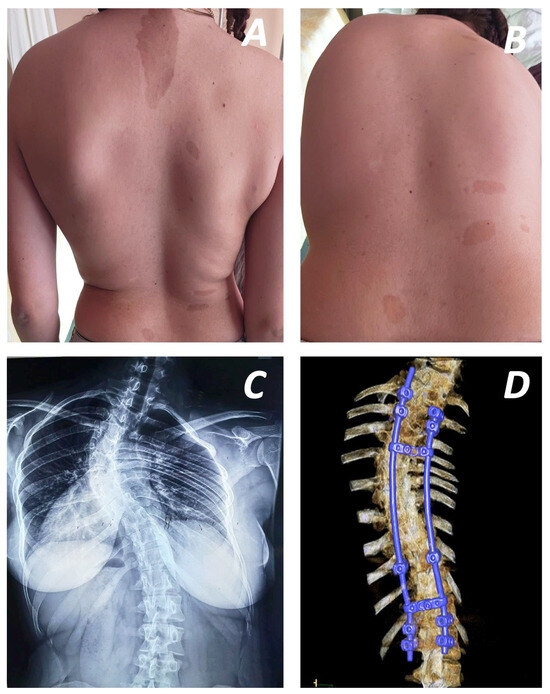

Tips and Pitfalls of Surgical Techniques for Scoliotic Deformities in Neurofibromatosis Type 1

by Angelos Kaspiris, Ioanna Lianou, Vasileios Marouglianis, Roberta-Spyridoula Afrati, Evangelos Sakellariou, Andreas Morakis, Panagiotis Karampinas, Elias S. Vasilisadis and Spiros G. Pneumaticos

J. Clin. Med. 2026, 15(1), 104; https://doi.org/10.3390/jcm15010104 - 23 Dec 2025

Background: Neurofibromatosis 1 is an autosomal dominant disorder accompanied by extensive early-onset spinal manifestations, with or without dystrophic scoliotic features. While non-dystrophic subtypes can often be treated similarly to idiopathic scoliosis, dystrophic scoliosis typically requires more aggressive intervention, often involving instrumentation in [...] Read more.

Background: Neurofibromatosis 1 is an autosomal dominant disorder accompanied by extensive early-onset spinal manifestations, with or without dystrophic scoliotic features. While non-dystrophic subtypes can often be treated similarly to idiopathic scoliosis, dystrophic scoliosis typically requires more aggressive intervention, often involving instrumentation in severely compromised pedicles or vertebrae. Purpose: This review aims to present recent advances in the surgical treatment of Neurofibromatosis 1-associated scoliosis, including surgical techniques and emerging guidance methods. Methods: An electronic literature search was conducted in Web of Science and PubMed to identify surgical techniques for scoliosis in patients with Neurofibromatosis 1. Results: Forty-one studies on the operative treatment of dystrophic scoliosis or both subtypes were retrieved. Although aggressive treatment with combined anterior and posterior fusion are widely used, posterior-only methods, which avoid plexiform tumours, present encouraging results. Recent studies highlight the effectiveness of growing rod systems in early-onset cases, enabling delayed fusion while preserving T1-S1 growth. Promising results from sectional or segmented correction techniques demonstrate better sagittal balance and Cobb angle correction, respectively. Preoperative use of halo-gravity traction, which has been extensively studied, is associated with reduced neurological impairment and encourages better correction results, avoiding autofusion. Various studies have also reported more precise pedicle screw placement with guidance of O-arm and triggered electromyography (t-EMG). Conclusions: The correction of spinal scoliotic deformities presents a significant challenge. However, recent advances in surgical techniques and intraoperative guidance offer promising strategies for more effective management. Full article